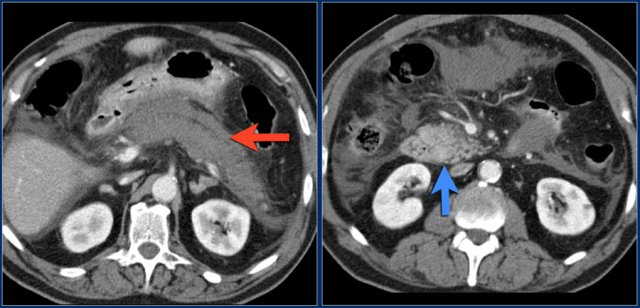

The upper images are of a patient with liver cirrhosis and multifocal hepatocellular carcinoma examined after contrast injection at 2.5ml/sec.

Because of poor enhancement the examination was repeated at 5ml/sec.

There is far better contrast enhancement and better tumor detection.